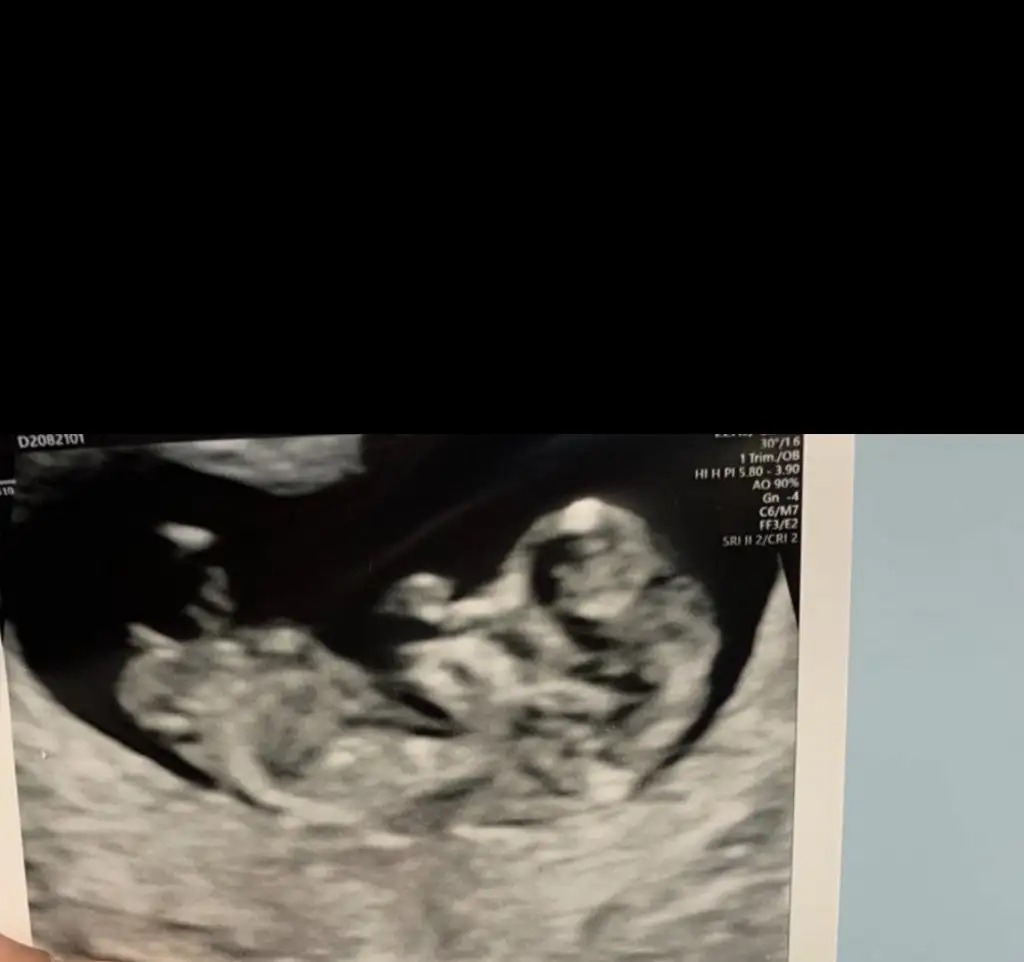

Benim demek istedigim arkadasin biri demisti kafa sekli kiz gibi diye aglakasi yok kiz oglan koydum ikisinin kafasi ayni sekilKizlar size iki tane resim biri kizima biri ogluma ait sizce hangisi kiz hangisi erkekEki Görüntüle 2657161 Eki Görüntüle 2657162

Erkek bencedeKızlar bana da tahminde bulunur musunuz doktor erkeğe benziyor dedi ama benim hala umudum var belki kız olur diyeEki Görüntüle 2656674